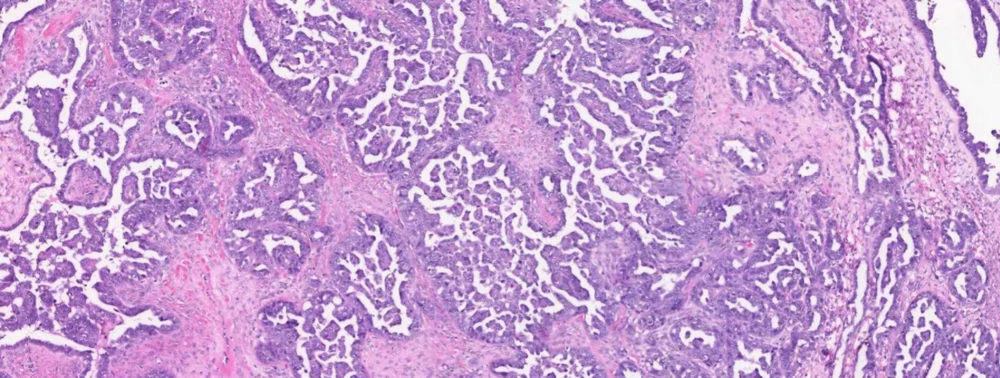

Experimental image-based AI models are very good at extracting new information from standard H&E pathology slides. However, the biological interpretation of these novel findings is a challenge. In this webinar, Dr. Anna Laury, Clinical Researcher at the University of Helsinki, will explain how they used scanned H&E slides of high-grade serous carcinoma of the tube/ovary (HGSC) together with spatially resolved transcriptomics to explore whether AI findings actually represent biological differences in these tumors.

High-grade serous carcinoma of the tube/ovary (HGSC) is characterized by aggressive behavior, chemotherapy resistance, and low 5-year survival, but also exhibits striking variability in outcome. Our understanding of this disease is limited, partly due to considerable tumor heterogeneity, and predicting any individual patient’s response to therapy is challenging.

Dr. Laury’s team used Aiforia® Create to train an AI model to predict patient outcome in HGSC by identifying tumor regions that are highly associated with outcome status. The tumor regions identified by the AI model are currently indistinguishable by pathologists. They then used spatially resolved transcriptomics to profile these AI-identified tumor regions and identify molecular features related to disease outcome.